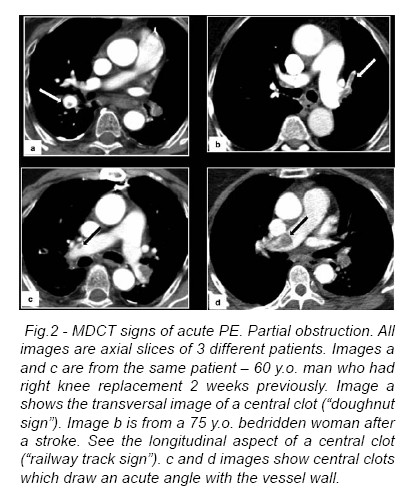

Nonobstructive Filling Defect

A nonobstructive filling defect may be central or eccentricin location. On angiography, a central filling defect is completely surrounded by contrast material. On CT, this finding is seen as a well-defined central filling defect in either an axial or a longitudinal plane with respect to the vessel. A nonobstructive central filling defect cannot float within the center of the lumen without physically touching the vessel wall and will be attached to either a nonobstructive eccentric filling defect or the thrombus of complete obstruction. In acute PE, a nonobstructing eccentric filling defect forms acute angles with respect to the vessel wall when seen on angiography orCT (Fig.2).